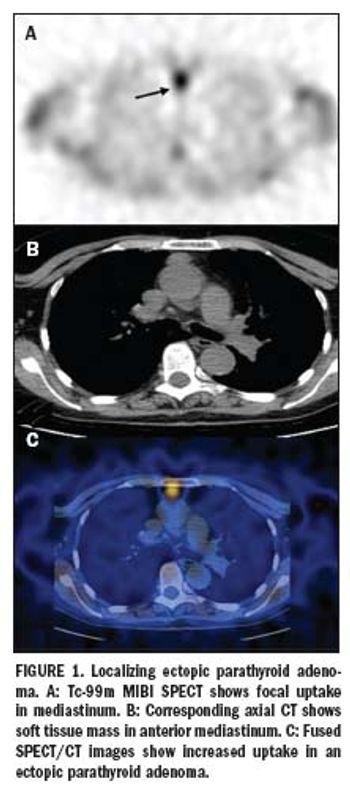

Standard nuclear scintigraphy of parathyroid cancer produces enough false positives for patients with multigland disease to lead researchers to recommend rapid intraoperative parathyroid hormone assay along with preoperative technetium-99m sestamibi imaging to assure that all lesions have been removed.